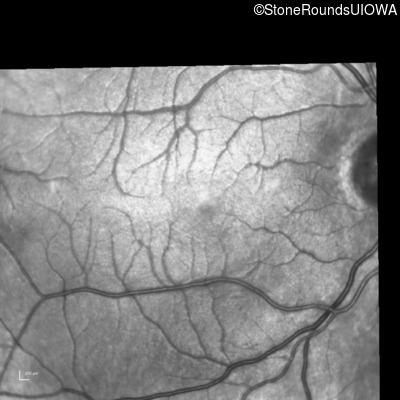

Age at visit: 17 years

OD OS

This 17 year old male had normal vision until about 6 months earlier when he began to lose central vision. The left eye may have been affected prior to the right eye.